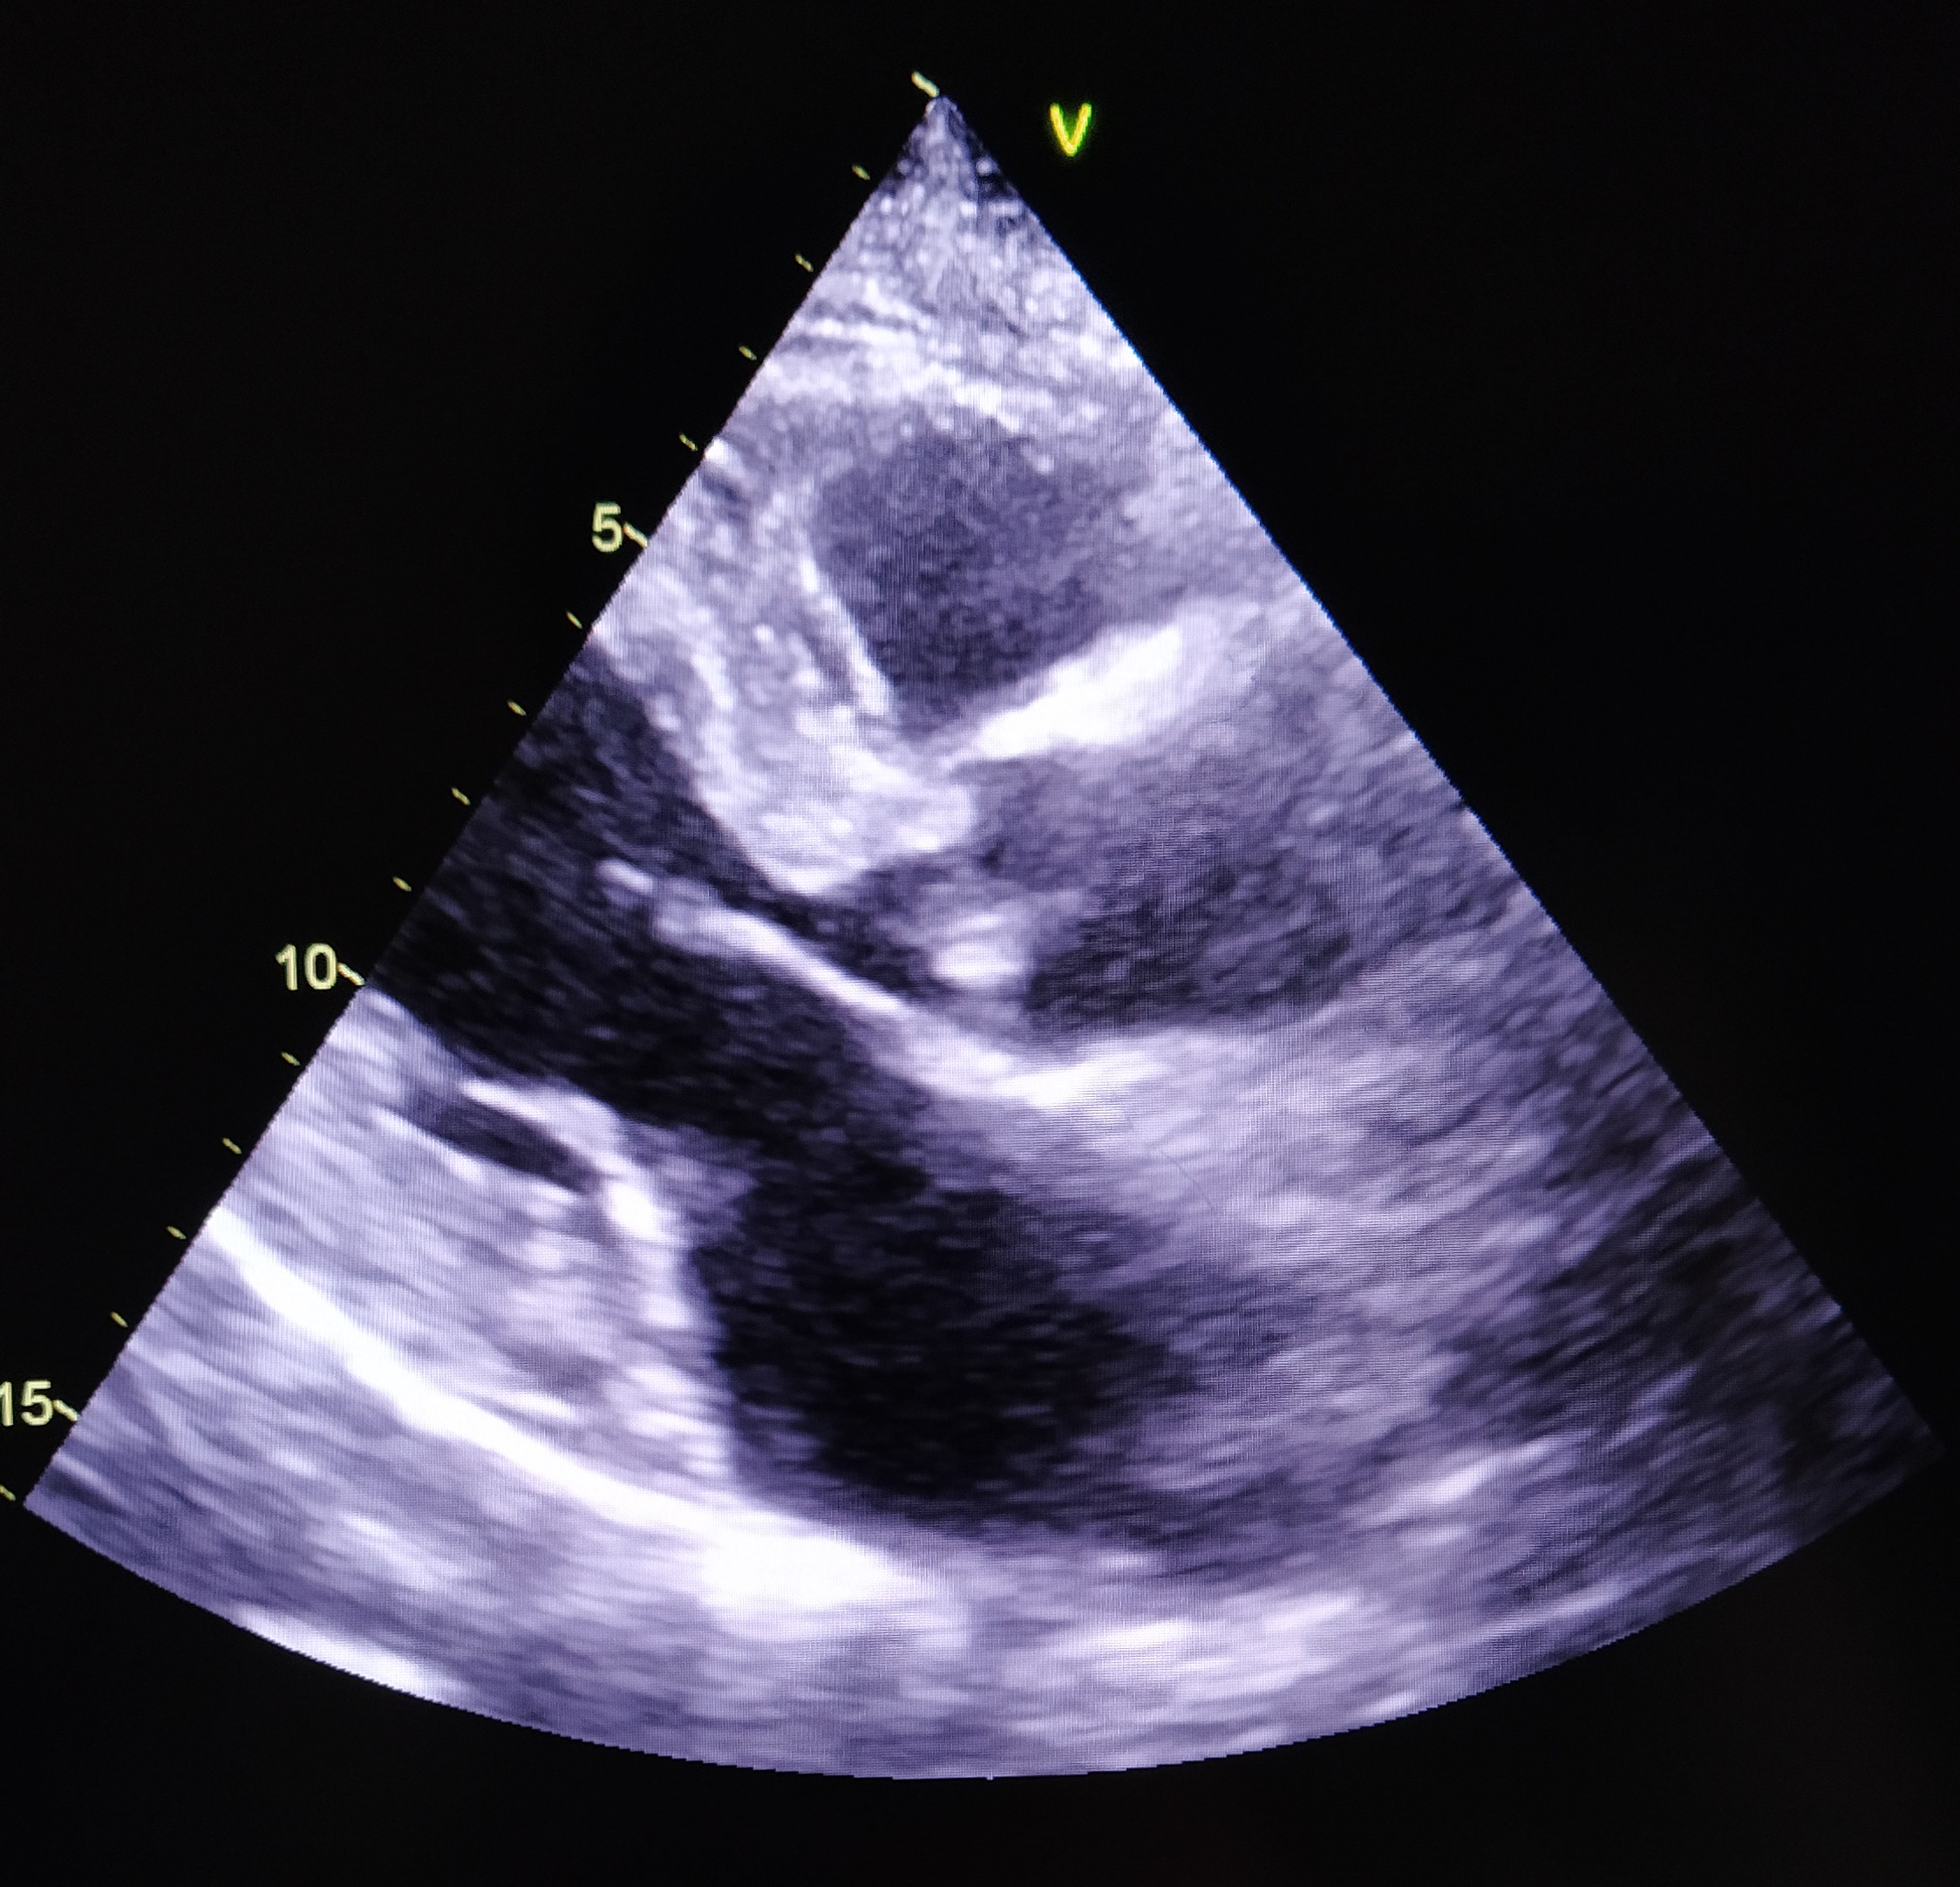

Resim 1b. Aort Kapağı Üzerinde 0.9 × 0.6 cm Boyutlarında Ölçülen, Okla Gösterilen Vejetasyonun Transtorasik Ekokardiyografi (TTE) Görüntüsü

Üç farklı zamanda alınan üç set kan kültüründe aynı etkenin üremesi, kalıcı kateterin geç çekilebilmesi ve aort odağında yeni gelişen bir üfürüm duyulması nedeniyle bakteriyeminin 11. gününde yapılan transtorasik ekokardiyografi (TTE)’de aort kapakta ventrikül tarafında 0.9 × 0.6 cm boyutlarında vejetasyon saptandı (Tablo 1, Resim 1a-1b). Kültür ve TTE sonuçlarıyla iki majör kriteri sağlayan hastaya S. maltophilia endokarditi tanısı kondu.